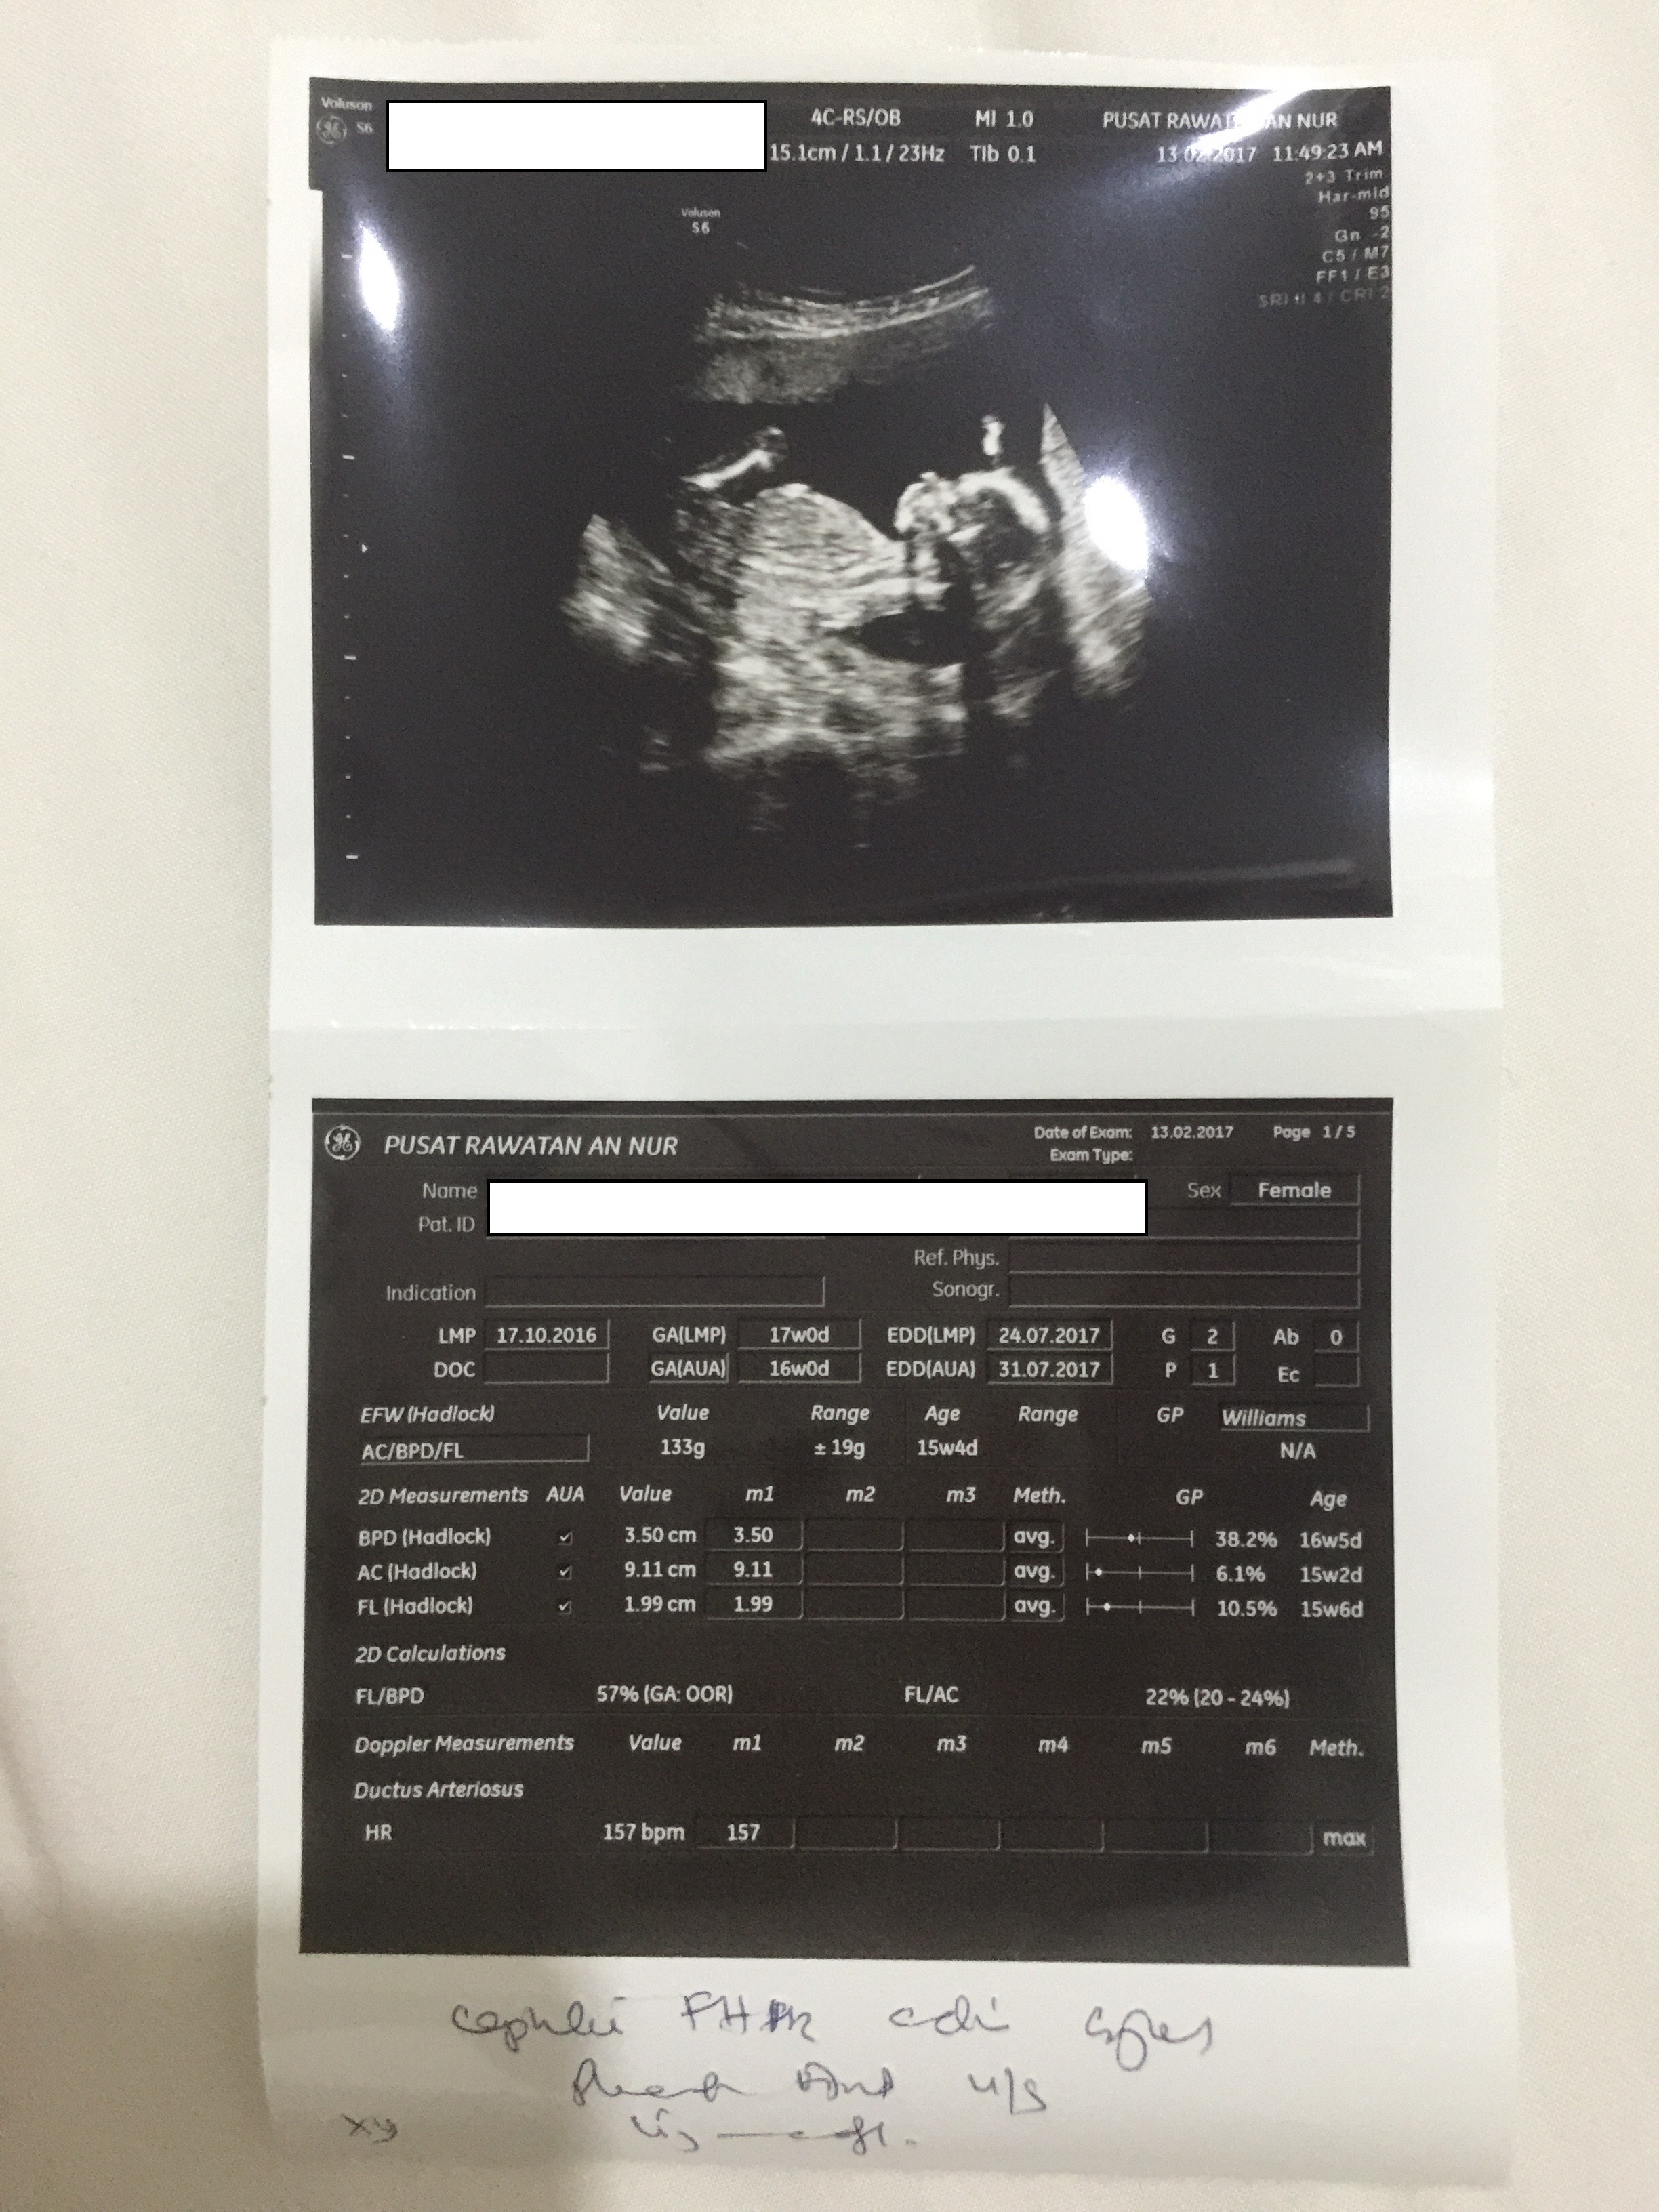

- Alhamdulillah sudah memasuki minggu 16/17 kamdungan.

- Memeriksa di Poliklinik An Nur di Batu Berendam untuk 2D scan pada 13 feb.

[Updated March 13,2017]

- Scan 2D